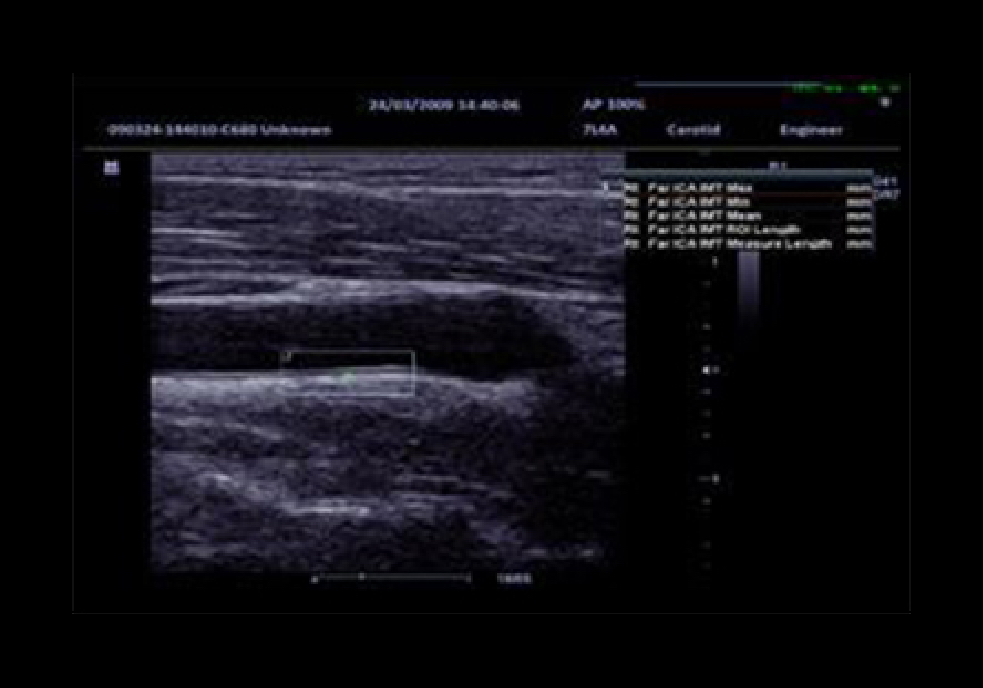

IMT (Intima-Media Thickness)

Auto measurement of anterior and posterior wall thickness providing accurate carotid status.